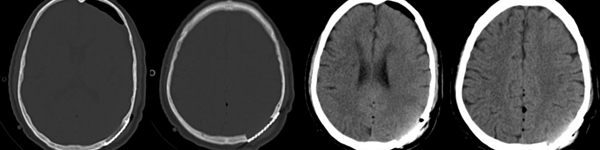

术中可见肿瘤组织位于切口中心,予以完整切除并修补硬膜缺损。根据3D打印支架形态,个体化设计钛网材料行颅骨缺损修补术后复查头颅CT,左顶部肿瘤全切除,左顶部颅骨缺损一期钛网修补完好。

术前及术后颅骨三维重建对比